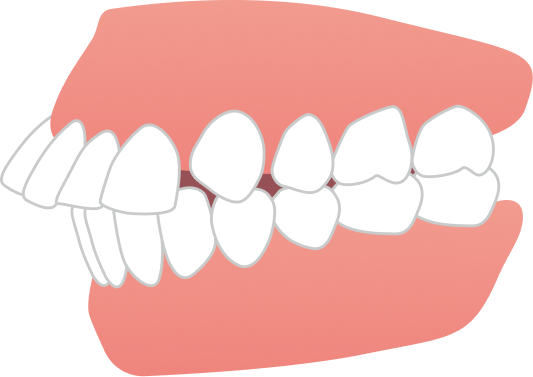

スタート時19歳の大学生女性の患者さまで、上下の前歯のガタつきに加え、「前歯で噛めない」「噛みにくく食事がしづらい」という機能面のお悩みもあり、ご相談に来院されました。学業や日常生活への影響をできるだけ抑えながら治療を進めたいというご希望を踏まえ、当院で専門的に行っているマウスピース矯正にて治療を開始しました。

治療期間は1年8ヶ月で、大学生のうちに治療を終えることができました。見た目の改善だけでなく、噛み合わせも整い、前歯でしっかり噛めるようになっています。

BEFORE

AFTER

| 施術内容 | 歯全体のマウスピース矯正システム「インビザラインフル」を用いた治療 |

| 治療期間 | 1年8ヶ月 |

| 費用 | 924,000円(税込) |